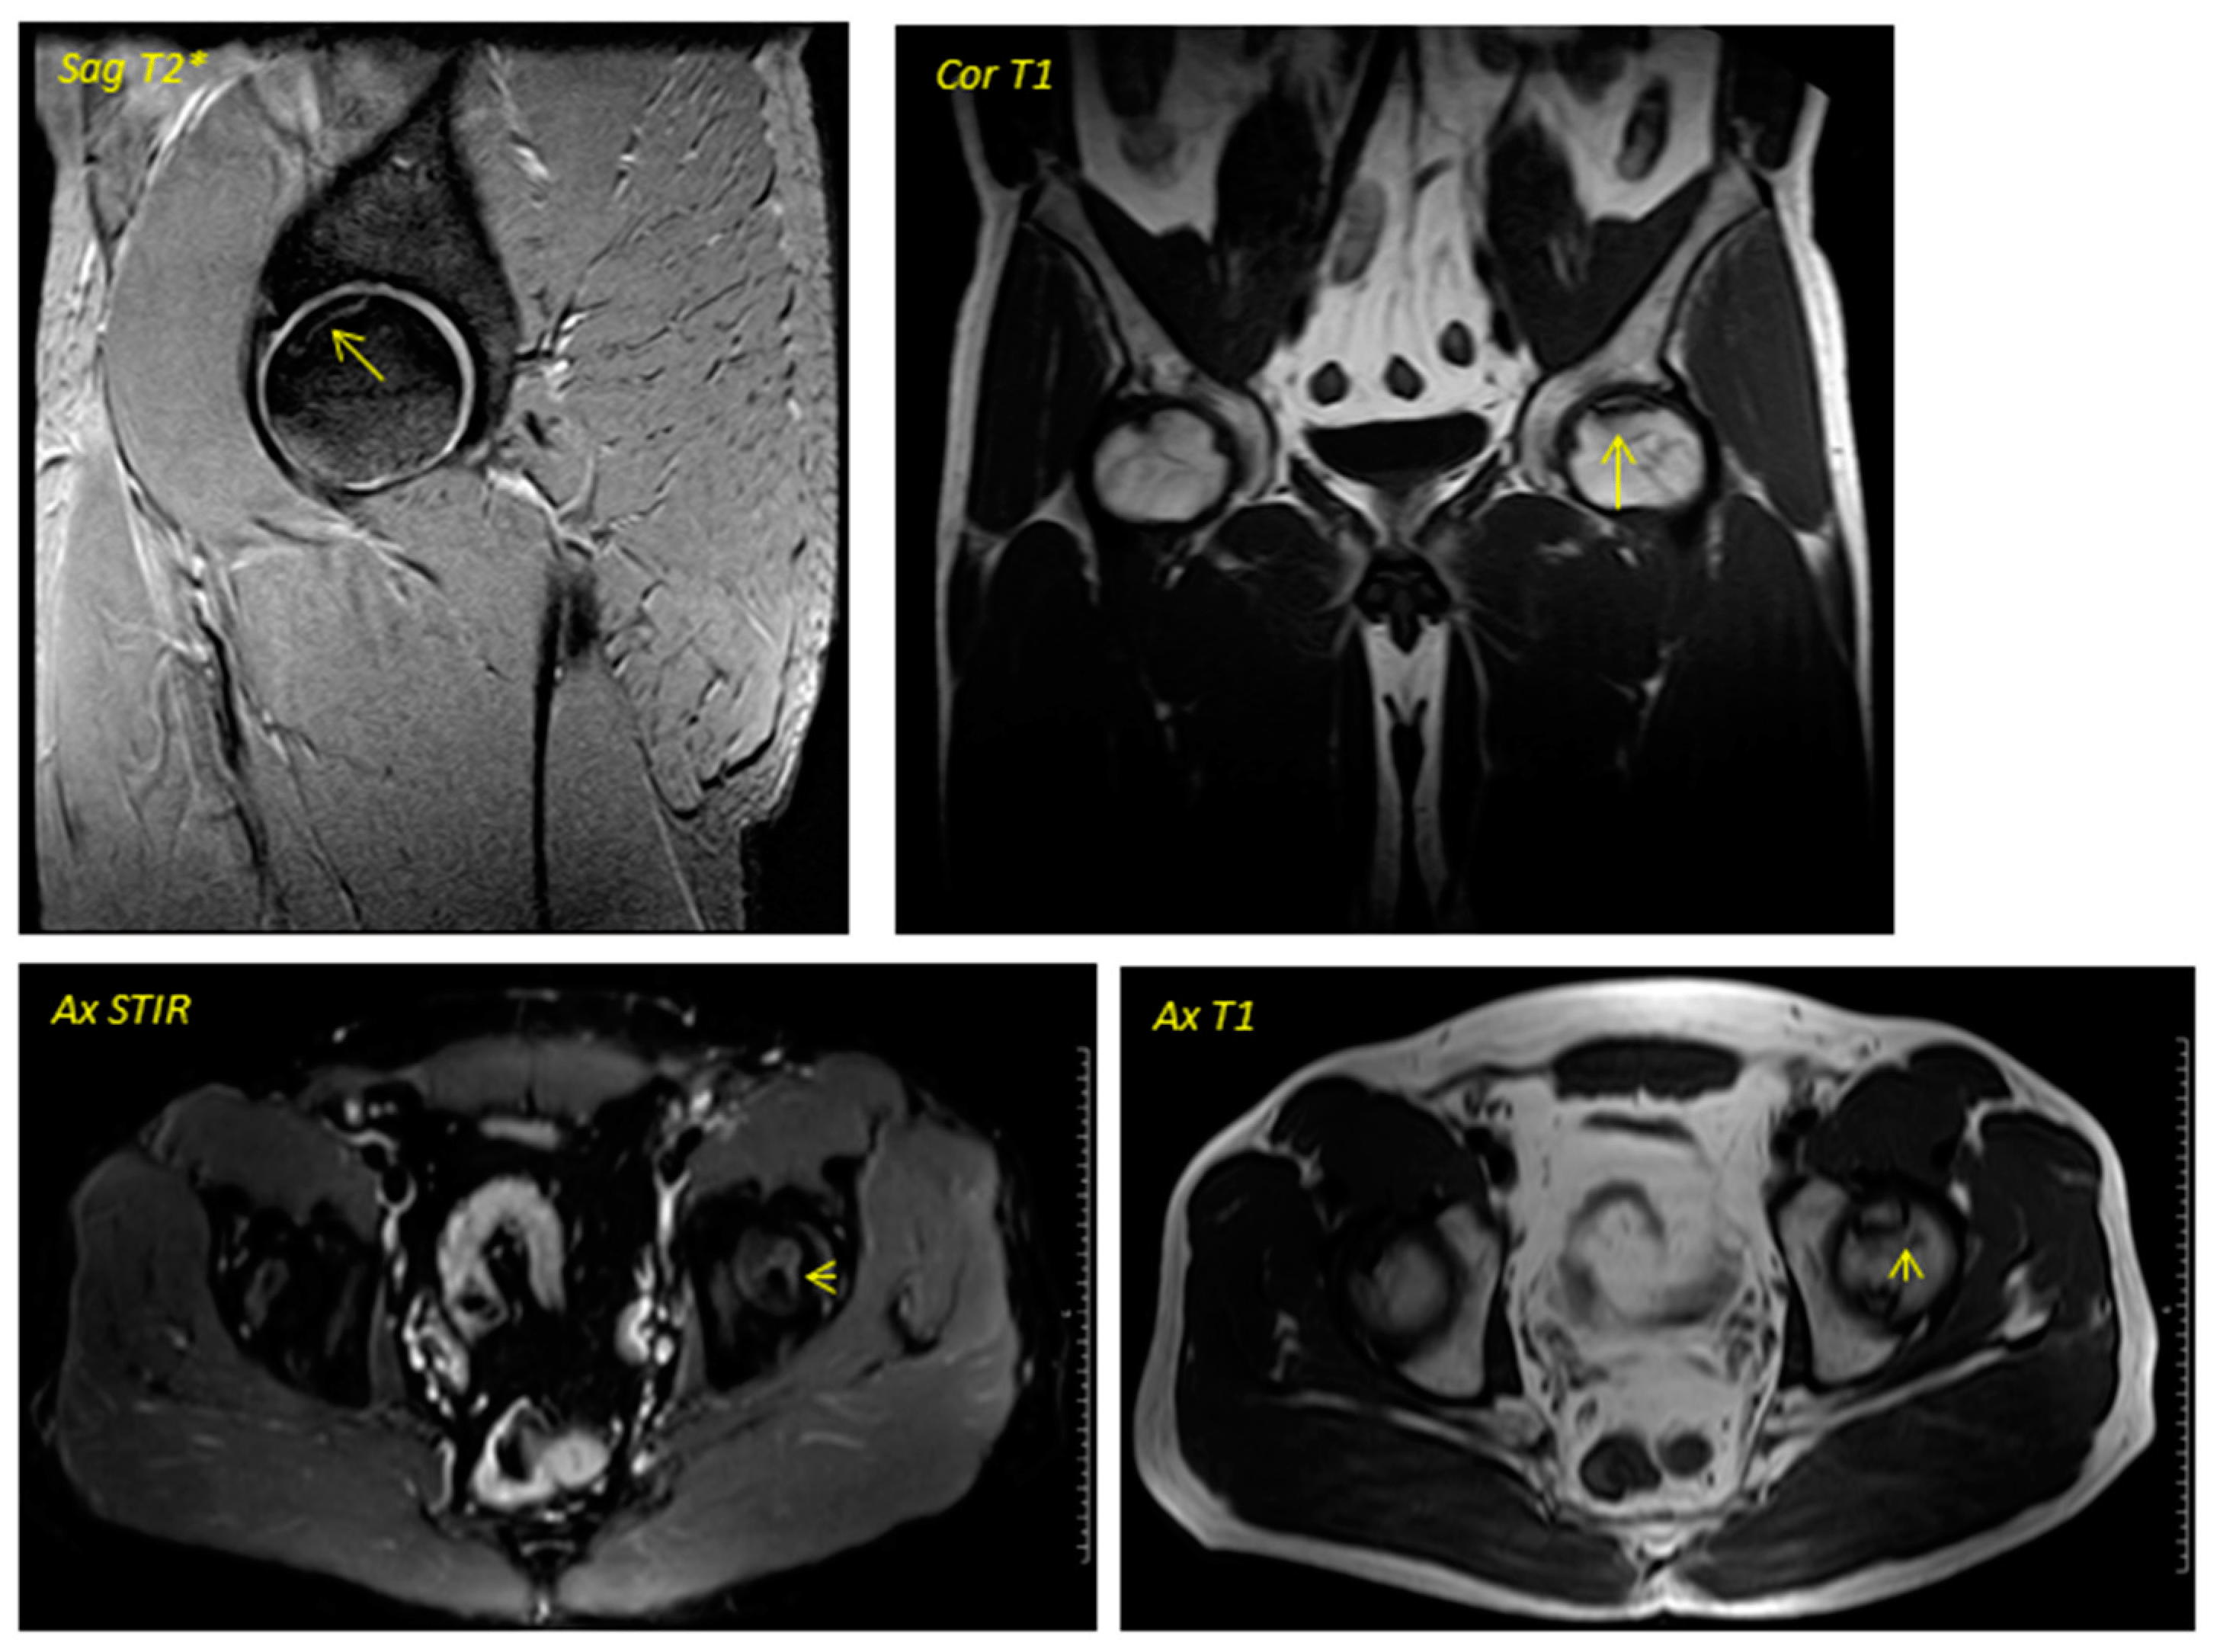

關于影像學研究,在12個月的隨訪期間,在影像學演變中觀察到了一些發現(圖1和圖2)。

首先,方向的變化從第六個月開始出現在所有病例中,而在早期階段并不明顯。其次,62.5%的患者 ( n=5) 在手術后的第一年內實現了影像穩定。第三,兩名患者 (25%) 出現壞死區進展,而一名 (12.5%) 患者出現明顯的再骨化跡象。盡管觀察到描述性差異,但后一個參數的p值在統計學上并不顯著。